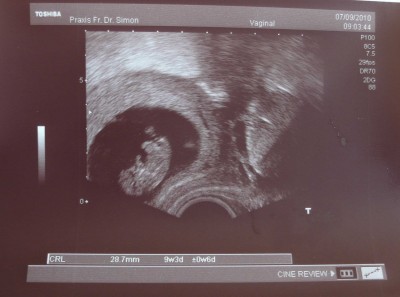

Hi, die VU war super!!! Meine Blutwerte sind alle perfekt (nur mein Blutdruck war mit 100 zu 72 zu niedrig), und wegen der Schilddrüse soll ich mich mal bei einem Internisten durchchecken lassen. Unser Kleines ist jetzt 2,9cm groß & hat während des US wunderschön gestrampelt (Papa war ganz begeistert *g* )! Meinen MUPA habe ich jetzt auch endlich, dafür muss ich bis zum nächsten Termin jetzt 4 laaange Wochen warten!

Das Bild ist echt toll :lol: und schön das alles ok ist!

@ Maiar: Glückwunsch zum Mutterpass. Dein Krümel ist voll süß. :juhu: Hoffe, Deine Übelkeit lässt bald nach und die vier Wochen gehen schnell vorbei.

@Liebe Maiar-Steffi: WOW, das ist ein echt superschönes Bildchen :P Voll niedlich und man kann alles so super erkennen!!! Wahnsinn, wie super ein US-Gerät funktionieren kann. Herzlichen Glückwunsch zum MuPa :knuddel: :knuddel: . Vier Wochen sind heute noch lang...aber in 3 Wochen und 5 Tagen nicht mehr :wink: , die Zeit rennt bestimmt bis dahin und ich freue mich sehr für Dich!!!! Weiterhin gute Besserung wegen der Shit-Übelkeit. Ich hoffe, Deine Schilddrüsenwerte können abgeklärt werden und Dein Blutdruck ist echt niedrig. Was machst Du nun dagegen?